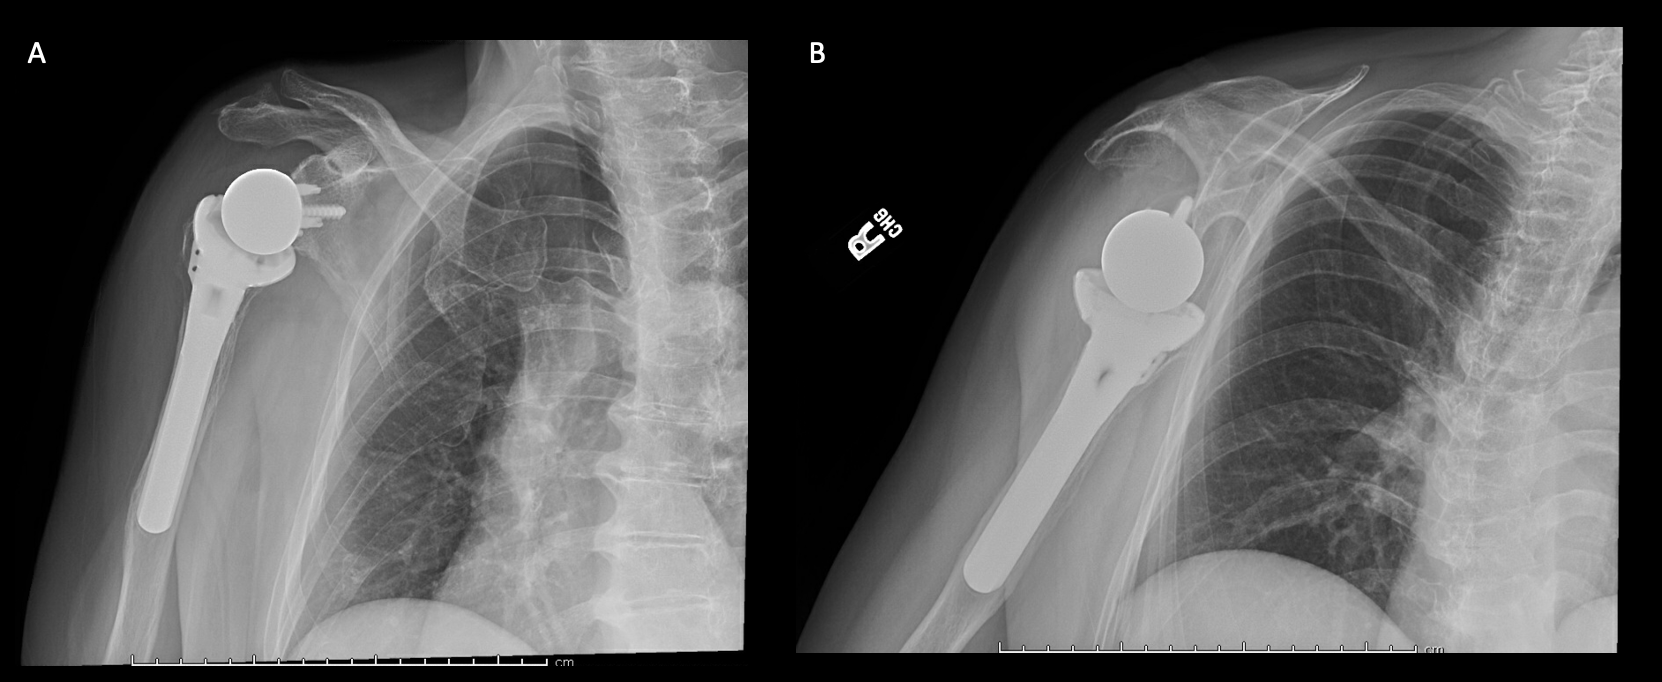

A 69-year-old woman presented after resection arthroplasty of her right shoulder hemiarthroplasty and completion of antibiotic treatment for culture negative PJI for evaluation of reconstructive options. She had a history of a displaced two-part right proximal humeral fracture which was repaired with an intramedullary nail. Post operatively, she had persistent pain and CT scan of the shoulder showed two screws in the humeral head that extended through the cortex and into the glenohumeral joint. The screws were removed and replaced with smaller screws. Subsequently, she had non-union of the fracture in the setting of deltoid weakness and was revised to a right hemiarthroplasty (Figures 1-3). Post operatively, she had persistent pain refractory to physical therapy and diminished function that was impacting her quality of life. She sought subsequent care, and there was concern for arthroplasty failure secondary to a septic versus aseptic condition and the decision to proceed with resection arthroplasty was made. During resection arthroplasty, a significant amount of fluid was expressed from the joint space. The combination of the clinical picture of progressive and persistent pain and the gross expression of fluid were concerning for PJI and the decision to treat was made. It was felt that the extent of humeral bone loss did not allow for a stable cement spacer, so none was placed. Intraoperative joint fluid cultures, anaerobic, and fungal cultures were all negative for growth. Cultures were held for 21 days to rule out C. Acnes infection. Considering the plan for future reimplantation, infectious disease consultation recommended a 6-week course of vancomycin but after 2 days the patient had a transfusion reaction and was switched to daptomycin. She was left with markedly limited active motion associated with severe pain. After completion of the antibiotic course, the patient elected to proceed with revision surgery. This patient had a flattened and distorted glenoid and atrophied rotator cuff musculature demonstrated prior to resection arthroplasty on CT (Figure 4). This patient’s prior hemiarthroplasty had been a tantalum coated, cemented humeral stem with associated marked thinning of the humeral cortex even prior to resection arthroplasty, and this resulted in a large amount of proximal humeral bone loss during the resection (Figure 5). The patient was severely debilitated by the right shoulder and wanted to proceed with reconstruction. Because of the combination of glenoid and humeral bone loss and the lack of rotator cuff attachments, a custom constrained prosthesis design process was initiated, and the implant was available 16 months after the resection arthroplasty. Preoperative 3 phase SPECT (Single Photon Emission Computed Tomography) three phase bone scan, upper extremity CT, and blood work (WBC 5.4, ESR 9, CRP 0.8) showed no suggestion of active infection.

A 62-year-old woman presented for evaluation of her reconstructive options after resection arthroplasty of a right rTSA and completion of antibiotic treatment for culture negative PJI. Her rTSA had been an Encore prosthesis placed due to rotator cuff arthropathy (Figures 6). Post-operatively she had persistent pain, stiffness, and tenderness to palpation that was treated with physical therapy, a steroid injection, and manipulation under anesthesia. An infectious work up due to the chronic and persistent nature of the pain showed WBC 7.4, ESR 53, CRP 1.2. Patient denied further work up with a tagged white cell scan and preferred continued clinical monitoring to observe pattern of symptoms. Eleven months later, she endorsed persistent pain. Repeat infectious work up showed WBC 4.5, ESR 13, and CRP 1.1. Despite the normal inflammatory markers, a 10-day trial of Augmentin was initiated and failed to change her symptoms. The decision to proceed with 1 vs 2 stage reconstruction was made. During resection arthroplasty, a substantial amount of fluid was expressed from the joint capsule concerning for PJI. A cement spacer was placed, and the patient was treated with 6 weeks of vancomycin and cefepime (Figure 7). There was proximal humeral bone loss as the result of resection arthroplasty due to the humeral stem. The glenoid component was loose and associated with glenoid bone loss, further complicated by the need for removal of a broken central screw (Figure 8).